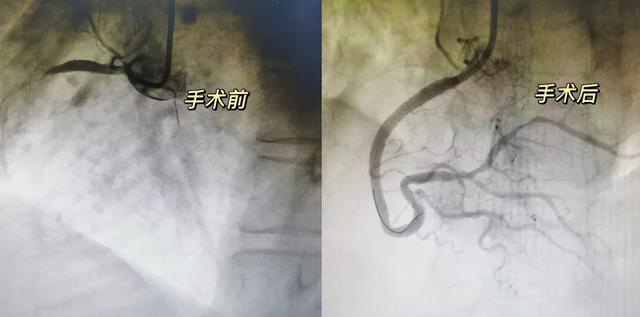

(▲术前右冠近段完全闭塞,术后右冠开通血流恢复。)

12月9日,陆胜主任主刀为患者实施心脏造影与支架植入术,凭借精准判断与娴熟技术,成功打通生命通道。术后,他每日查房,用通俗语言细致讲解康复要点,以责任与专业安抚家属焦虑。